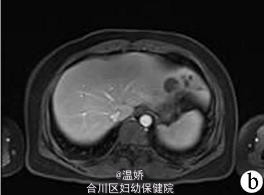

人肝片形吸虫病1例报告

患者,女,41岁,因肝区胀痛2个月余人院。2个月前无诱因出现肝区胀痛,伴发热(体温最高38℃),当地医院予抗感染后疼痛症状缓解,体温下降但此后症状时有反复发作。入院1d前当地医院腹部CT平扫提示肝左叶低密度灶。